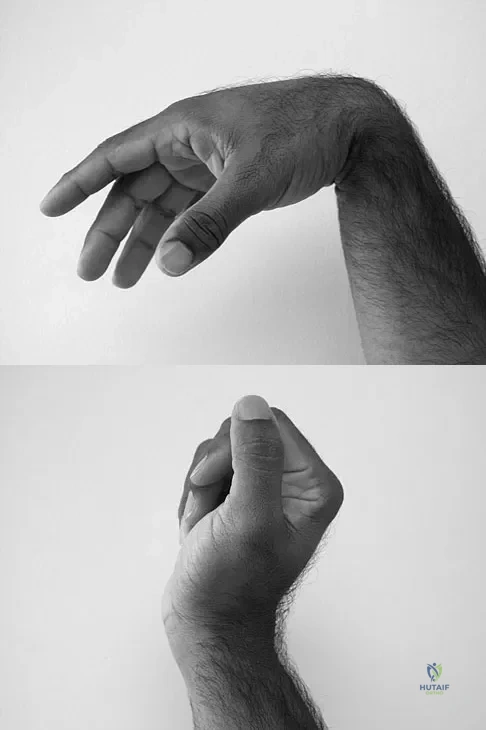

Question 91

A 35-year-old man sustained a 1-inch stab incision in his proximal forearm while trying to use a screwdriver 2 weeks ago. The laceration was routinely closed, and no problems about the incision site were noted. He now reports that he has been unable to straighten his fingers or thumb completely since the injury. Clinical photographs shown in Figures 30a and 30b show the man passively flexing the wrist. What is the most appropriate management?

Explanation